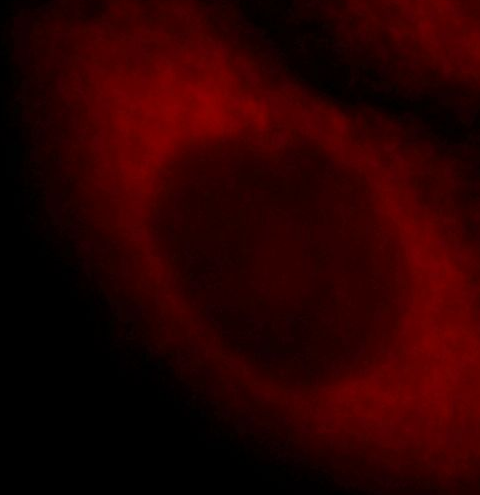

Immunofluorescent analysis of HepG2 cells, using SCIN antibody FNab07635 at 1:25 dilution and Rhodamine-labeled goat anti-rabbit IgG (red). IP Result of anti-SCIN (IP:FNab07635, 4ug; Detection:FNab07635 1:300) with human placenta tissue lysate 2800ug.